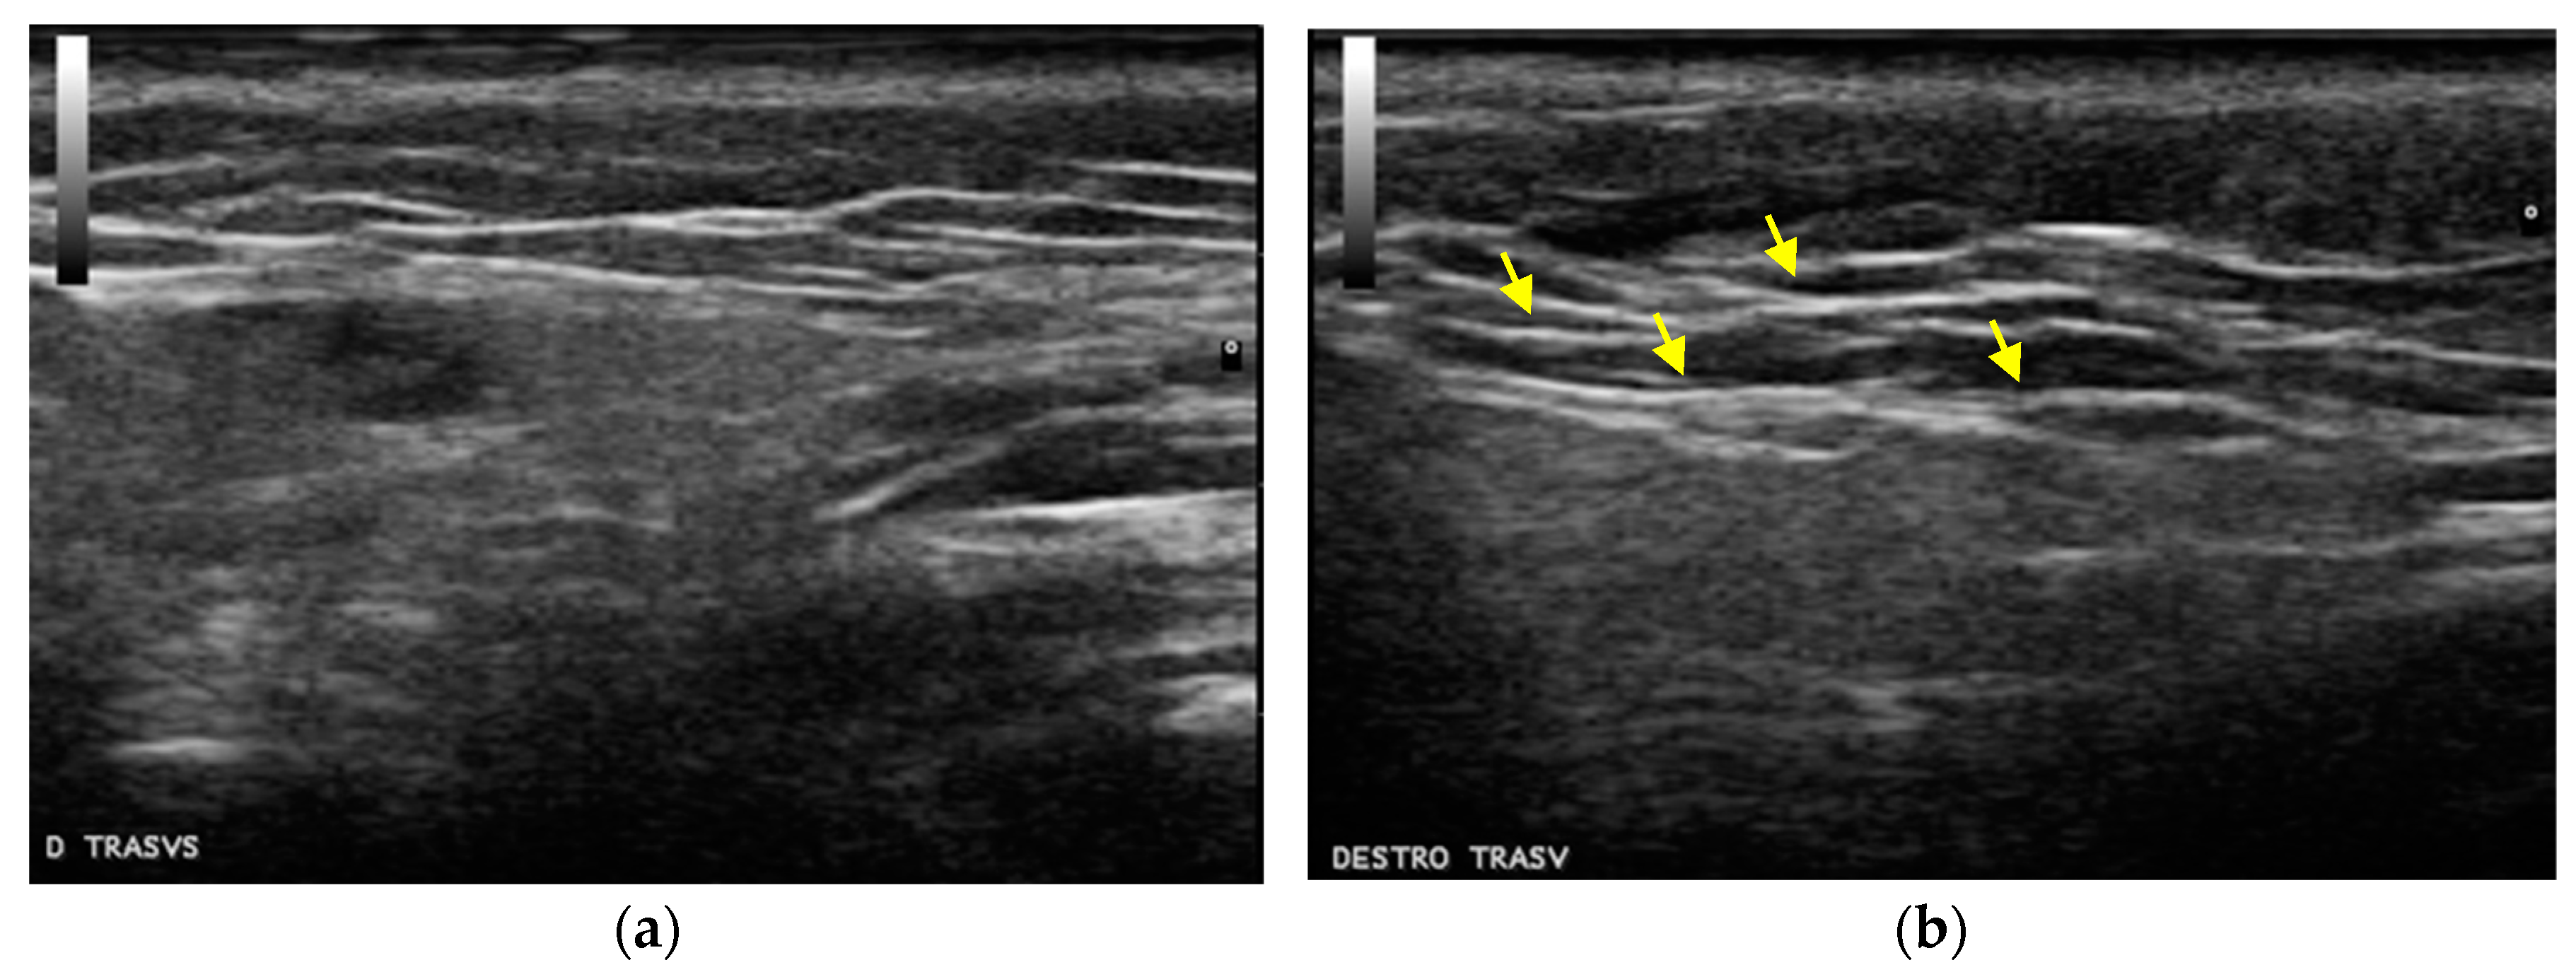

2.1. Cohesivity

2.2. Clinical Evaluations

4.4. Instrumental Evaluations

4.5. Clinical Evaluations